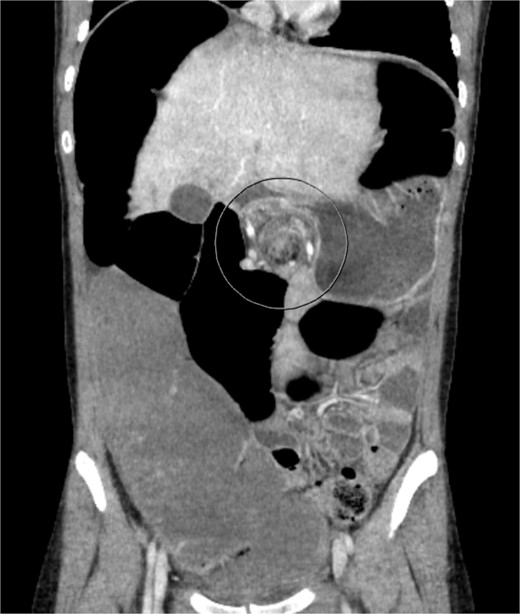

A 19-year-old female presented to the emergency department with complaints of epigastric abdominal pain, nausea, vomiting, and having passed no gas or bowel movements for 4 days. Her past medical history consisted of irritable bowel syndrome, gastroparesis, depression and anxiety, eosinophilic esophagitis, and opioid abuse. She did not take any medication for her depression and anxiety. Her past surgical history included upper and lower endoscopy and surgical ablation of genital warts. She has a significant family history of a brother who has ulcerative colitis. Upon physical exam, her abdomen was tympanic and distended. There was epigastric tenderness with no guarding or rebound tenderness. Due to concern for a bowel obstruction, a nasogastric tube was placed, and a computed tomography (CT) scan was done (Fig. 1). Imaging showed immense distension of the colon due volvulus at the splenic flexure with narrowing of the mesenteric vasculature and free fluid in the abdomen. The patient was taken for an exploratory laparotomy emergently with a preoperative diagnosis of a large bowel obstruction due to internal hernia versus volvulus. During the operation, it was found that the distal transverse colon was the point of obstruction and showed scarring with dilatation proximal to the narrowing, and there was no internal hernia identified. An extended right colectomy was performed with ileocolic anastomosis. She had a return of bowel function on postoperative Day 4. Six days post-operation, the patient began to have nausea and vomiting and had not had a bowel movement in 2 days. Eight days post-operation, a CT scan was performed that illustrated proximal small bowel dilatation (Fig. 2). With concerns of another bowel obstruction, an exploratory laparotomy was performed. During the operation, a dilated small bowel and a twisted sigmoid colon were found consistent with a large bowel obstruction secondary to sigmoid volvulus. A completion colectomy with end ileostomy was performed.

CT of the abdomen performed on Day 1 of admission. Shows colonic distension with volvulus at the splenic flexure.